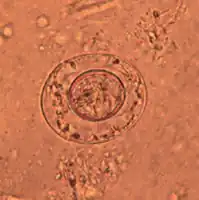

An egg of dwarf tapeworm

As its name implies (Ancient Greek: νᾶνος, nānos – dwarf), it is a small species, seldom exceeding 40 mm long and 1 mm wide. The scolex bears a retractable rostellum armed with a single circle of 20 to 30 hooks. The scolex also has four suckers, or a tetrad. The neck is long and slender, and the segments are wider than long. Genital pores are unilateral, and each mature segment contains three testes. After apolysis, gravid segments disintegrate, releasing eggs, which measure 30 to 47 μm in diameter. The oncosphere is covered with a thin, hyaline, outer membrane and an inner, thick membrane with polar thickenings that bear several filaments. The heavy embryophores that give taeniid eggs their characteristic striated appearance are lacking in this and the other families of tapeworms infecting humans. The rostellum remains invaginated in the apex of the organ. Rostellar hooklets are shaped like tuning forks. The neck is long and slender, the region of growth. The strobila starts with short, narrow proglottids, followed with mature ones.